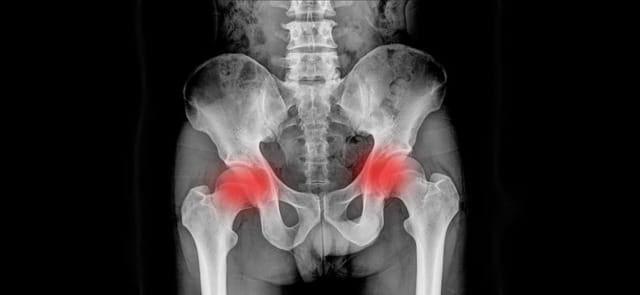

Сакроилеит

• рентгенография, компьютерная и магнитно-резонансная томография. Необходимы для установления факта разрушения хрящевой ткани, эрозии костей, воспаления мышечных волокон.